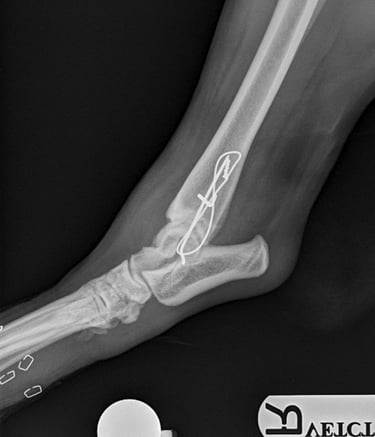

Orthogonal xrays reveal a lateral malleolus fracture (Fig.1 and 2), stress views and palpation revealed stable joint with no affection of collateral ligaments but due to the fracture there is some degree of rotational instability. Surgical stabilization is strongly advised as Buddy is a 40 kg patient.

Lateral approach to the talocrural joint reveals severe oedema and bruising, 1.2mm IM pin placed in a distal to proximal fashion, 0.75mm cerclage wire used to create a figure-of-8 tension band. 1.4mm pin placed parallel to the talocrural joint from lateral to medial (Fig 3 and 4).

Fig. 2